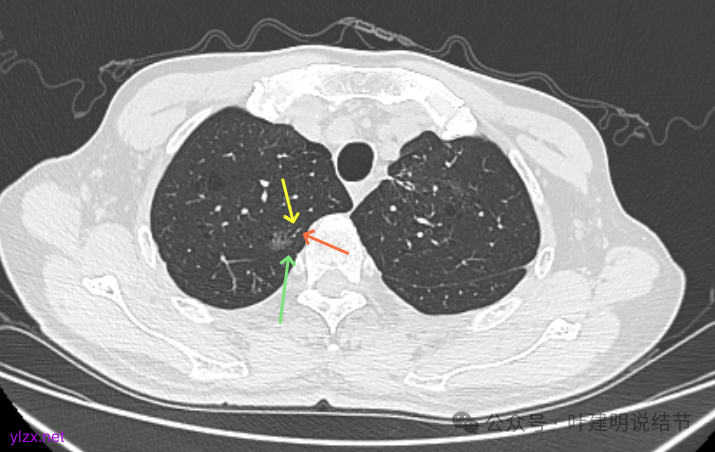

先看2020年9月的片子:

右上叶近脊柱旁有淡而纯的磨玻璃结节,整体轮廓与边界清楚,没有明显实性成分,也未见确切胸膜牵拉凹陷。

左上胸膜下有处偏长条小结节,也是磨玻璃密度的,轮廓较清。

左上叶前胸壁胸膜下有小结节,磨玻璃密度,有微小血管进入,轮廓与边界清。

左上叶混合密度结节,有毛刺与空泡征,瘤肺边界稍糊,灶内密度较为杂乱不均。